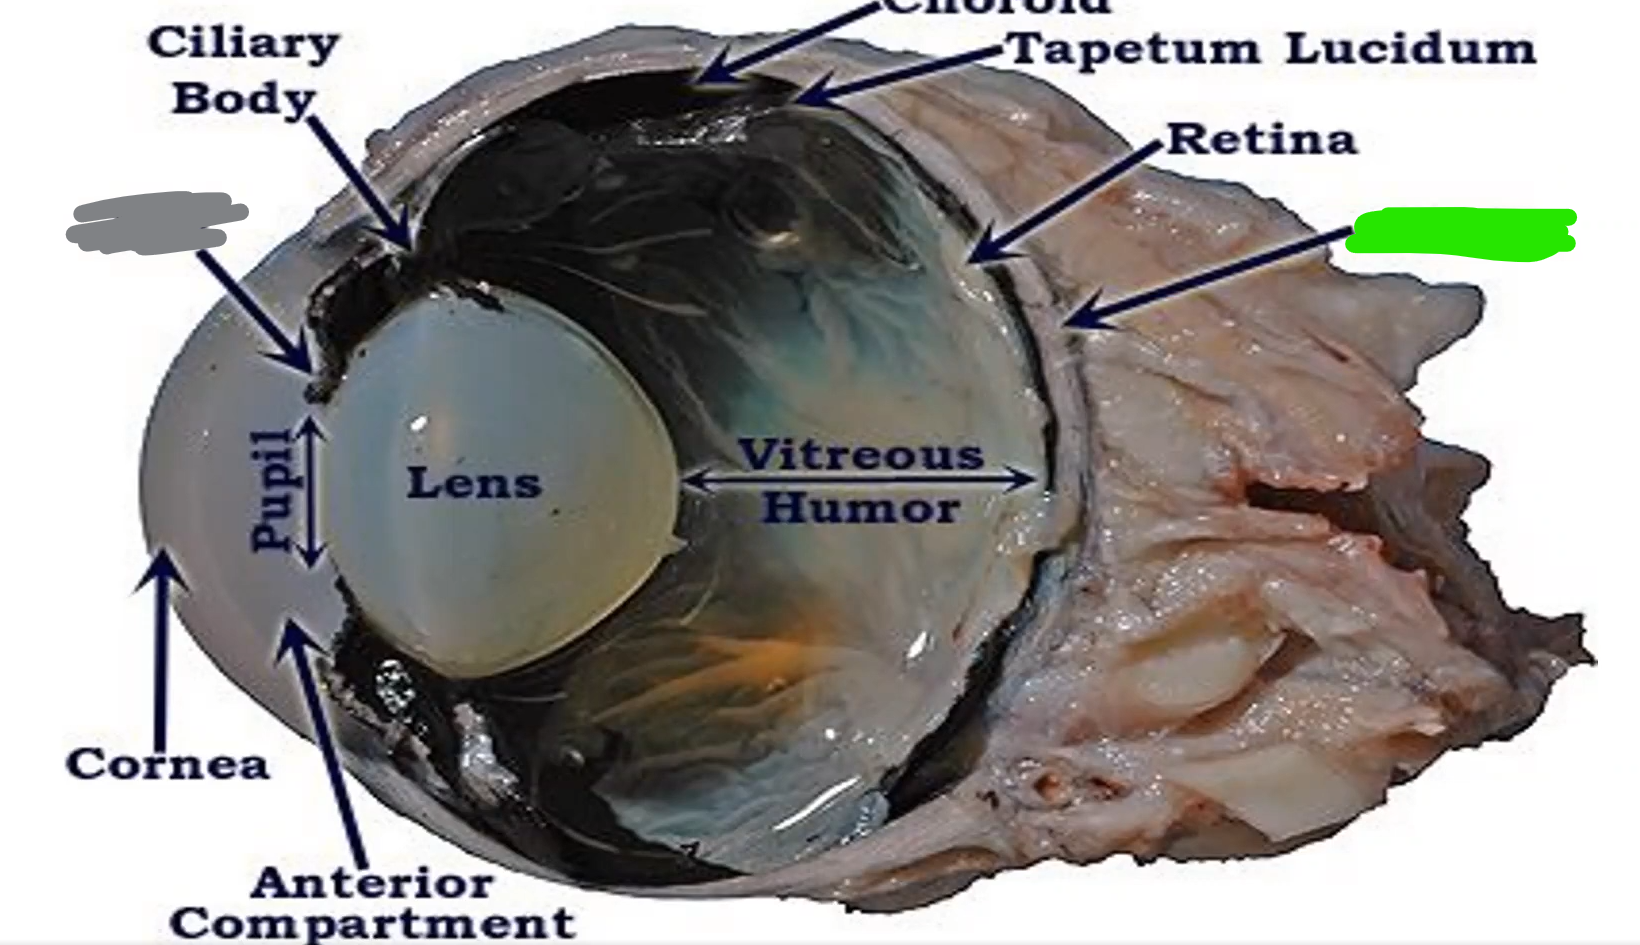

cornea

allows light, most sensitive part of body

Name

Ciliary body

controls shape of lens

Name

Choroid

Name

Tapetum

Name

Optic nerve

Orange name

Retina

Orange

Iris

Blue

Pupil/lens

Red

Lens

Blue

Retina

Green

vitreous humor

Gray

Iris

Green

Sclera

Blue

Pupil

Orange

Anterior compartment

Maintains pressure